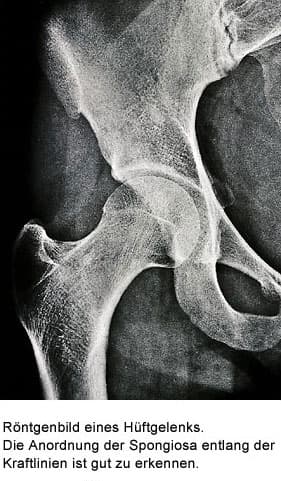

Knochen liegt in zwei verschiedenen Strukturen vor. Der kompakte Knochen, die „Compakta“, bildet die harte Röhre z.B. des Oberschenkel-Knochens. Der netzartige Knochen, die „Spongiosa“, liegt im Inneren der Kompakta, und zwar im Bereich der Knochenteile, welche die Gelenke bilden, und in den Wirbelkörpern.

Spongiosa

Die Spongiosa stützt die Gelenkflächen ab und überträgt die auftretenden Kräfte auf die Kompakta. Die geometrische Anordnung der Spongiosa folgt den Kraftlinien, die durch ein Gelenk wirken. Diese Kraftlinien werden Trajektorien genannt. Die gesamte Knochenmasse besteht etwa zu 80% aus Kompakta und zu 20% aus Spongiosa.